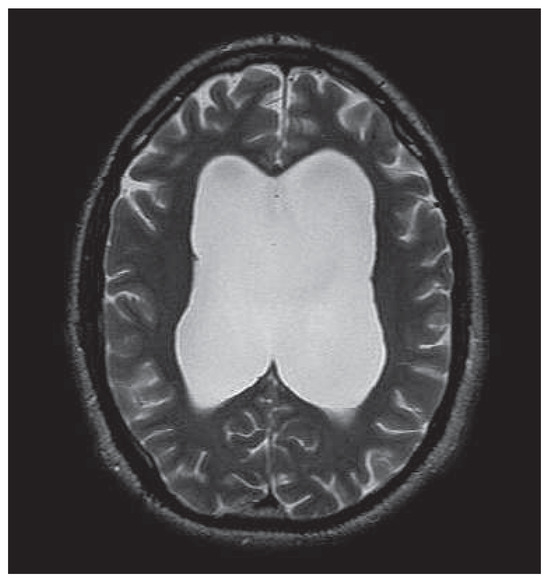

Hydrocephalus, psychosis and art: a case report

by Sarah Noll, Heinz Boeker, Gerold Roth-Greminger, Paul Hoff and Daniel Schuepbach

Objectives: Published evidence suggests a linkage between structural brain damage and psychotic symptoms. Internal hydrocephalus often manifests with neurological and psychiatric symptoms, which occur with great variety between individuals. Methods and results: We present a case of a male suffering from treatment refractory psychosis for years, and with a special talent for artistic painting. An enormous communicating hydrocephalus, which has probably existed for several years, was detected by means of anatomical neuroimaging. As the patient began to suffer from signs of high intracranial pressure such as headache and dizziness, an endoscopic third ventriculostomy was successfully performed. The neurological symptoms disappeared shortly after surgery, psychotic symptoms attenuated gradually and artistic work changed. Conclusions: This case is exceptional with regard to symptoms caused by a hydrocephalus and changes in artistic work, as an expression of executive function and abstract thinking, due to surgical intervention. It demonstrates the need to pay attention to cerebral lesions when confronted with neuropsychiatric symptomatology, especially if psychotic symptoms persist despite adequate antipsychotic treatment. Full article

Figure 1